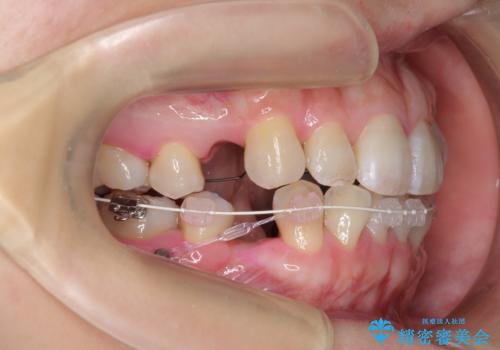

ハーフリンガル 犬歯のねじれ 歯根の外部吸収している歯を抜歯

- ハーフリンガル

- 前歯のねじれを主訴に来院。

レントゲンを撮影したところ、右下4は神経のない歯で、外部吸収といって、根がだんだん短くなり、やがて抜けてしまう症状になっていました。また、アンキローシスを起こしている可能性があるため、動かない可能性が高い状態でした。

矯正治療で右下を抜歯し、スペースを天然の歯でつめる矯正治療を行いました。